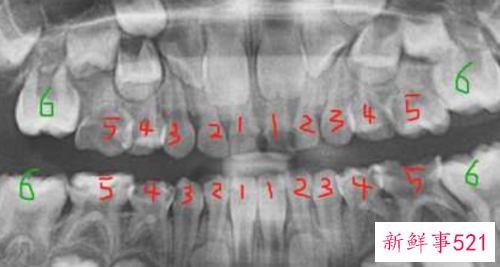

六岁左右,开始长六龄齿,加上四颗六龄齿,孩子的牙齿是24颗。(下图为六岁小孩全景片)